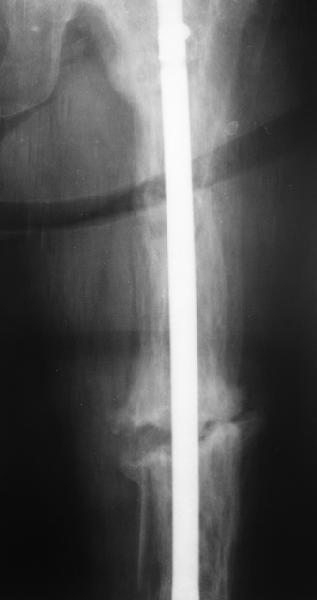

Еще один пример. Пациентка с юга России, прислала рентгенограммы через год. На сегодня прошло 2 г. 8 мес. после операции. Несмотря на не очень убедительный процесс сращения, пациентка ходит. Учитывая остеопороз при Педжете, решили, что динамизировать вообще не нужно.

При переломах на фоне болезни Педжета металлоконструкция часто служит эндопротезом, несущим нагрузку. Динамизация индивидуальна,- по рентген-динамике. Основной упор- на медикаментозную терапию- см. канд. дисс. Колондаева А.Ф.

Стержень можно было бы поставить подлиннее.

Анатолий Леонидович Баранецкий совершенно прав. Сращения ждать надо очень долго (несколько лет). Главное - гвоздь попрочнее и потолще. Раньше использовали мощный 4-гранный штифт ЦИТО. Можно и гвоздь с блокированием (блокировать только с одной стороны) - но ни в коем случае не полый. И ходить с тростью. Сейчас в России зарегистрирован очень хороший препарат (с декабря 2006 г.) - Акласта, по 100 мл - обычно хватает 1 (реже двух) инфузии для полной ремиссии (в Белоруссии он появился даже раньше, чем на Украине и в Россиии). Немного хуже Аредия, ее надо в сумме 180-240 мг, полная эффективность 84%. Все в\в кап. бисфосфонаты вызывают выраженную гипокальциемию. Поэтому приходится назначать по нескольку лет альфакальцидол под контролем Са крови (каждые 3-6 мес). Сперва по 6-8 капсул (капель), т.е 1,5-2,0 мкг, затем через 2-4 месяца - по 0,5-0,75 мкг. Препараты Са по 1-2 гр. в день, очень долго.